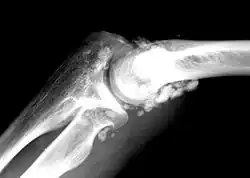

| X-ray of an elbow affected by synovial chondromatosis | |

Synovial chondromatosis is a locally aggressive bone tumor of the cartilaginous type.[1] It consists of several hyaline cartilaginous nodules and has the potential of becoming cancerous.[1]

In the early stages of the disease it is often confused with tendinosis and/or arthritis. Once it reaches transitional the loose bodies become apparent with X-ray in greater than 70% of cases, with MRI often showing where xray fails. In experienced hands, ultrasound is also useful for the diagnosis.[2]

Rare and little known, with currently no known cure, the disease gradually forms blisters in the thin flexible membrane of the synovium, which calcify and enlarge. These nodules eventually break free and float around the joint space becoming larger – these add to the discomfort and stiffness of the joint. The affected tissue will show up as a semi-solid mass in an MRI scan, final diagnosis is usually confirmed by taking a biopsy. The disease generally affects only one of the larger weight bearing joints (hip, ankle, knee) – although the elbow, and wrist can also be affected. It rarely involves the temporomandibular joint (TMJ) and most publications are case reports.[3]